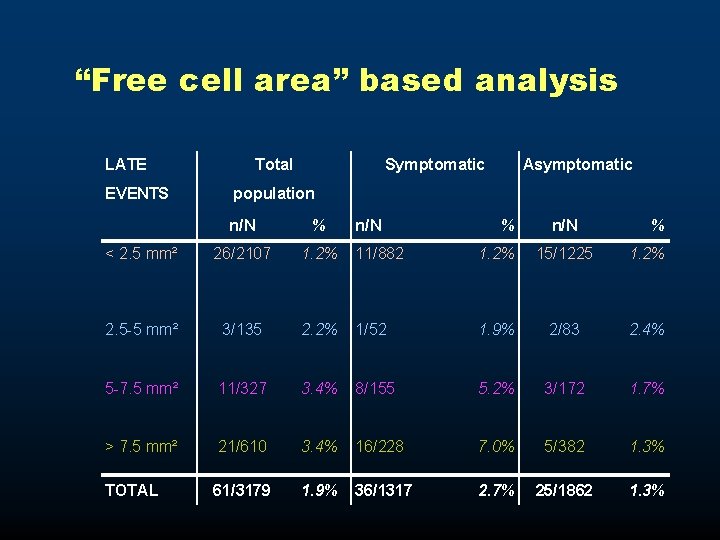

“Free cell area” based analysis LATE EVENTS Total Symptomatic Asymptomatic population n/N % < 2. 5 mm² 26/2107 1. 2% 11/882 1. 2% 15/1225 1. 2% 2. 5 -5 mm² 3/135 2. 2% 1/52 1. 9% 2/83 2. 4% 5 -7. 5 mm² 11/327 3. 4% 8/155 5. 2% 3/172 1. 7% > 7. 5 mm² 21/610 3. 4% 16/228 7. 0% 5/382 1. 3% TOTAL 61/3179 1. 9% 36/1317 2. 7% 25/1862 1. 3%